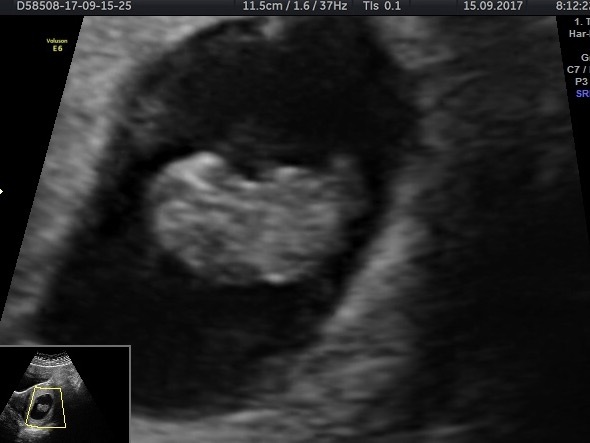

Lovely scan pic, looks clear to me but if it wasn't clear enough then I'm definitely drinking tonnes of water this week in prep for mine like PPs have said

@RosesForBadgers , congratulations on the scan!!

roses, such a lovely scan! It's crazy how much bigger they get just from 8 weeks!

Congrats on your scan roses its a great pic. X

@rose what a lovely scan! Very baby like now, which is crazy!! I'd say you are delighted and hope you're still feeling well.